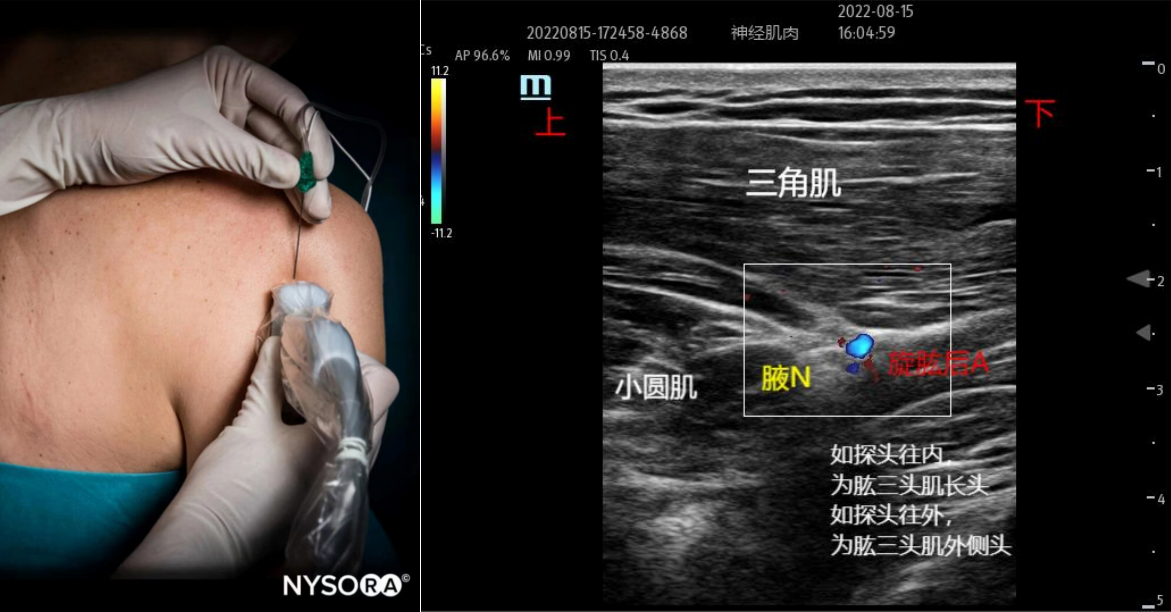

解剖关键点:旋肱后动脉、三角肌、肱三头肌。

扫查方法:探头矢状位放置于肩后部、腋窝后皮肤皱襞的正上方。缓慢向外侧扫查,出现肱骨声像时,辨别肱骨、三角肌、小圆肌、大圆肌和肱三头肌等结构。辨别肌肉可以采用追踪的办法。然后上彩色功能,找到旋肱后动脉,在旋肱后动脉周围寻找蜂窝状的腋神经。

穿刺方法:平面内法,从探头的上下两端进针均可。药物注射在神经周围,或者注射旋肱后动脉的周围也有效。